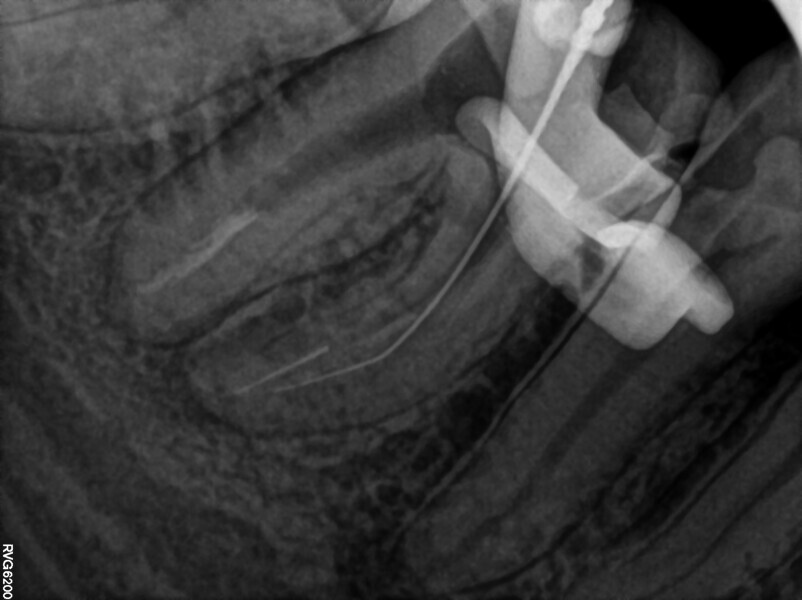

Fig. 20: Intra-op radiograph confirming lack of bypass and of patency.

After administering anaesthesia and placing a dental dam, the composite restoration was removed, and a temporary restoration with flowable composite and flowable dental dam for the root canal treatment was performed (Figs. 14–17). After removing the filling material from the mesiolingual and distal canals, access to the broken file was performed. The first piece of the instrument was removed with the ultrasonic tip (Fig. 18), and the tip of the second piece of the file then became visible. Unfortunately, the removed file piece broke in the middle and only the coronal part could be retrieved (Fig. 19). Because the apical part of the broken file was invisible and did not emerge from the canal during the irrigation and activation, an attempt at bypassing it was made. Analysis of the CBCT scan did not reveal a clear answer as to whether there was one apical foramen, so during the bypass procedure through the mesiolingual canal, a periapical radiograph was performed. The radiograph indicated that either there was a ledge in the apical area or there were two separate apical foramina (Fig. 20). For the irrigation protocol, the AutoSWEEPS mode was used at 1.2 W power with the flat SWEEPS 300/20 fibre tip. The tips of both mesial canals were placed below the orifice. The Less-Prep Endo protocol was performed twice in the manner described elsewhere.5 After the irrigation, irrigant flow between both canals was rapid.